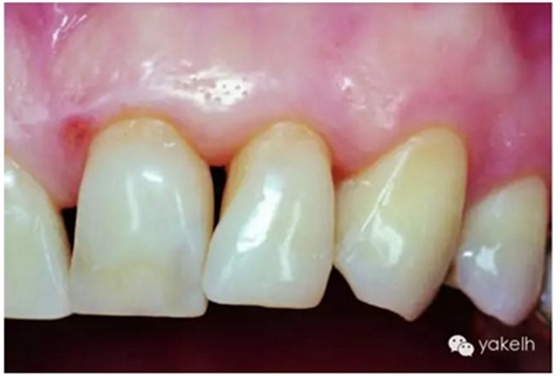

圖2.38用有熒光性的混合填料樹脂材料修復的修復體表現(xiàn)出和鄰牙渾然一體的亮度。

圖2.39修復體在紫外線光下顯示出極佳的熒光效應。